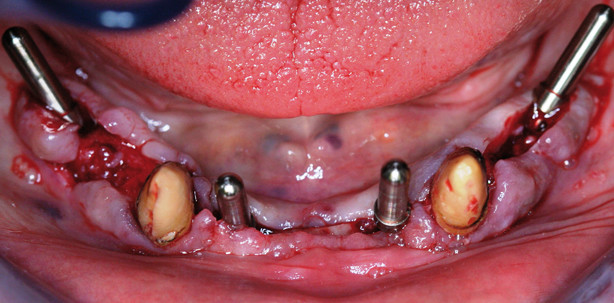

Nachdem die präzise Produktion und die Biokompatibilität mit knochenbildenden Zellen nachgewiesen war, wurde im Rahmen einer tierexperimentellen Untersuchung am Hund die schnelle Osseointegration (Knochenanlagerung an Implantatoberfläche) der F2- und Osseoinkorporation (Knochenanlagerung und Knocheneinwachsen in die dreidimensionale Implantatoberfläche) der F3-Implantate gezeigt. Bereits nach zwei Wochen der gedeckten Einheilung zeigten die F2-Implantate einen BIC-Wert (Knochen-Implantat-Kontakt) von 69 % (Abb. 8 und 9). Die F3-Implantate zeigten nach acht Wochen im Hund und sechs Monate im Menschen eine vollständige Integration im Knochen und ein knöchernes Einwachsen in die gesamte dreidimensionale Oberfläche (Abb. 10 und 11). Klinisch bestätigten sich die durchweg positiven wissenschaftlichen Erkenntnisse. Die F2-Implantate zeigen vorhersehbar sehr gute Ergebnisse bei allen Indikationen. So kann von Standard- über Sofortimplantationen auch jegliche Art von Augmentationen (ein- und zweizeitig) erfolgreich durchgeführt werden (Abb. 12–17). Und auch implantologische Konzepte wie angulierte Implantate mit abgewinkelten verschraubbaren Abutments (4 plus 6-Line) sind einfach durchführbar (Abb. 18–21).